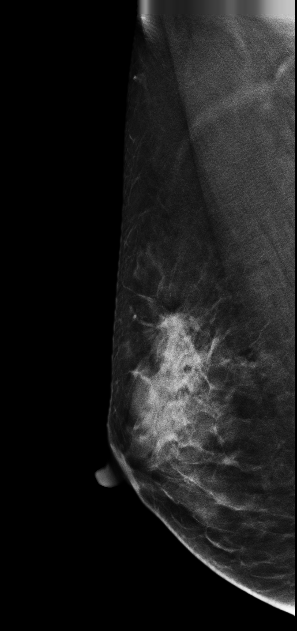

病例1 病史:患者 ,47y,右乳触及包块1。 2D图像

影像描述: 在2DMLO位图像的上象限发现一不对称局限性致密影,但CC位上未见明显异常病变区域,在V-Preview图像上MLO位上病变显示明显逼2D更清晰,在CC位上乳头后方深部我们可以清晰的发现病灶,在3D-plane图像上我们可以更进一步清楚观察到病变形态大小范围,以及病灶边缘呈星芒样长短不一毛刺样改变。 影像诊断: 右乳偏外象限局限致密影,考虑BI-RADS 4B 。 病例点评: 病理证实右乳浸润性导管癌,DBT可以给我们提供更多诊断信息有助于明确病变性质。